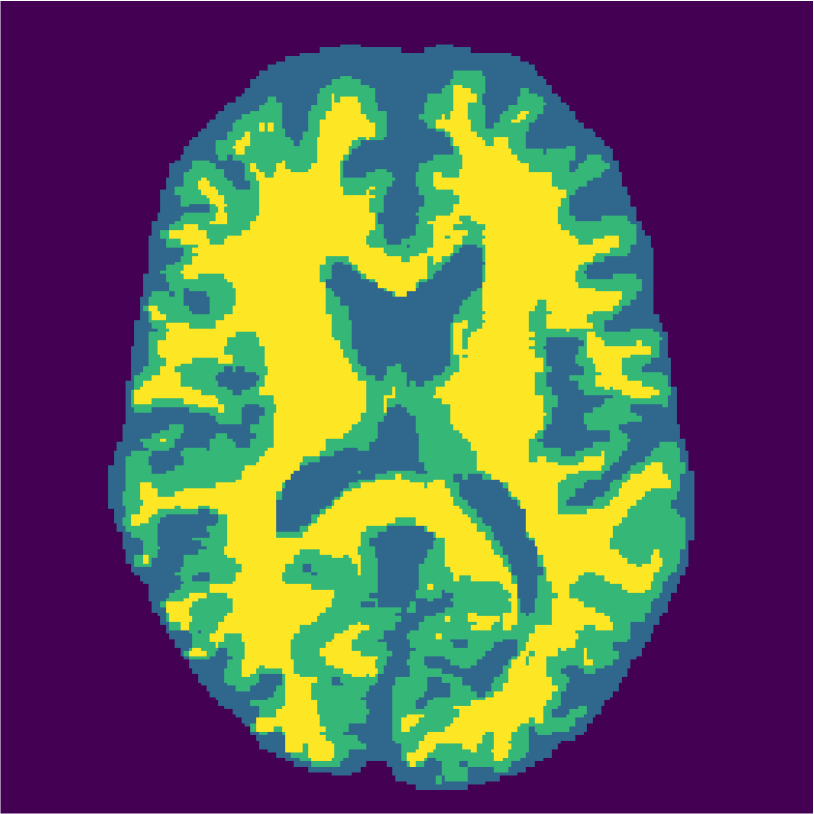

Examples of the segmentation results on one of the target test images are shown in Figure 8 for experiment 2.1, Figure 9 for experiment 2.2, and Figure 10 for experiment 2.3. Examples are shown after using 1 target patch per tissue for training, and after using 100 target patches per tissue for training. The results show that only the mrai-net classifier is able to predict a segmentation that approaches the ground truth with only 1 target patch per tissue for training (error for experiment 2.1 = 0.269, experiment 2.2 = 0.403, experiment 2.3 = 0.320), while the source and target classifiers cannot (source error for experiment 2.1 = 0.667, experiment 2.2 = 0.653, experiment 2.3 = 0.435; target error for experiment 2.1: 0.591, experiment 2.2: 0.614, experiment 2.3 = 0.596). After using 100 patches the source and target classifiers can predict a gross segmentation of WM, GM and CSF (source error for experiment 2.1 = 0.213, experiment 2.2 = 0.384, experiment 2.3 = 0.363; target error for experiment 2.1: 0.205, experiment 2.2: 0.368, experiment 2.3 = 0.368), but the mrai-net classifier prediction shows more details and a lower tissue classification error (error for experiment 2.1 = 0.111, experiment 2.2 = 0.276, experiment 2.3 = 0.284).

Appendix A describes the nuclear magnetic resonance (NMR) relaxation times for the tissues in the Brainweb anatomical models, for 1.5 and 3.0 Tesla field strengths. The tissues in the anatomical models are grouped into ”background” (BKG), ”cerebrospinal fluid” (CSF), ”gray matter” (GM), and ”white matter” (WM) to compose the ground truth segmentation labels for the simulated scans. The simulations result in images of 256 by 256 pixels, with a 1.0x1.0mm resolution. Figures 5(a) and 5(b) show examples of the Brainweb1.5T and Brainweb3.0T scan of the same subject. For all scans, we used a brain mask to strip the skull.

In order to test the proposed method on real data, we use the publicly available training data (5 subjects) from the MRBrainS challenge444http://mrbrains13.isi.uu.nl/Figure. The acquisition parameters used for simulating the Brainweb3.0T are based on the MRBrainS acquisition protocol (3.0T scanner, gradient-echo, B0 = 3.0T, = flip angle, TE = 4.5ms, and TR = 7.9ms). Figure 5(c) shows an example of an MRBrainS scan. Again, a brain mask is used to strip the skull.